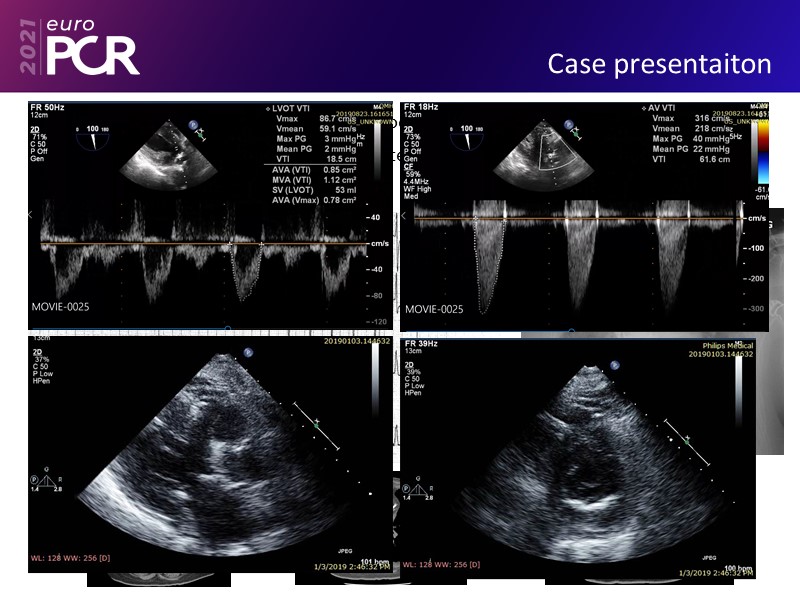

Leave no calcium uncracked--triple vessel disease, severe AS, cardiogenic shock EuroPCR 2021 Clinical Case SPEAKER: J. Fang Previous Next Download presentation